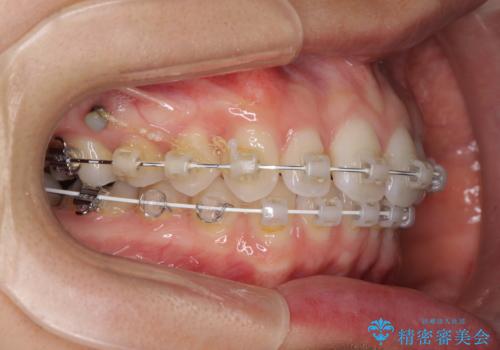

- 奥歯の虫歯と前歯のデコボコや突出感を気にして来院された患者様です。

上顎歯列が、下顎に対して前方にありましたが、口元に出っ歯の印象がなかったため、親知らずを抜歯した上で、上顎歯列全体を後方に移動させることとしました。

咬合力が強いため、アンカースクリューを使用し、ワイヤー装置にて矯正治療を行うこととしました。

上顎歯列を下顎に対して4mmほど移動させる必要があったため、治療は長期化することが予想されましたが、患者様にはこちらの期待以上にゴムかけなどに協力いただき、補綴治療も含めて2年強で終えることができました。